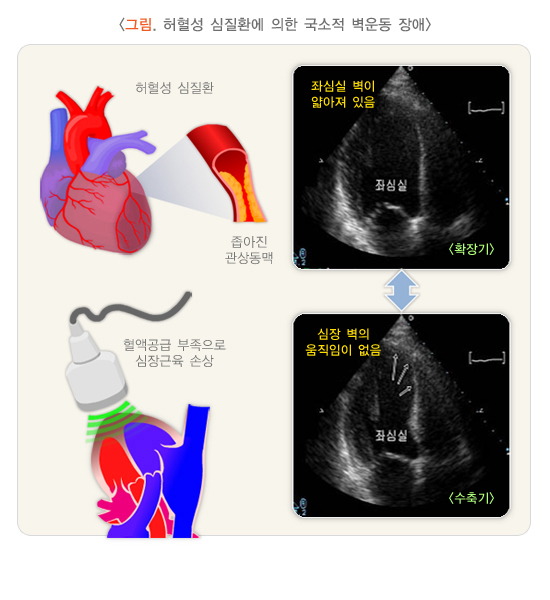

4) 허혈성 심질환의 평가

허혈성 심질환에서는 심장의 국소적인 심장벽의 움직임 장애를 확인할 수 있으며, 특히 사망률이 높은 심근경색의 감별진단에서 중요한 역할을 합니다.

2. 허혈성 심질환

허혈성 심질환이란 심장으로 혈액 공급을 담당하는 관상동맥의 이상으로 충분한 혈액 공급이 되지 않아 심장의 기능이 떨어지는 질환입니다. 흔히 협심증, 심근경색 등이 허혈성 심질환에 해당합니다. 질환이 발생한 관상동맥의 위치에 따라서 심초음파에서 국소적인 벽운동 장애가 관찰됩니다.